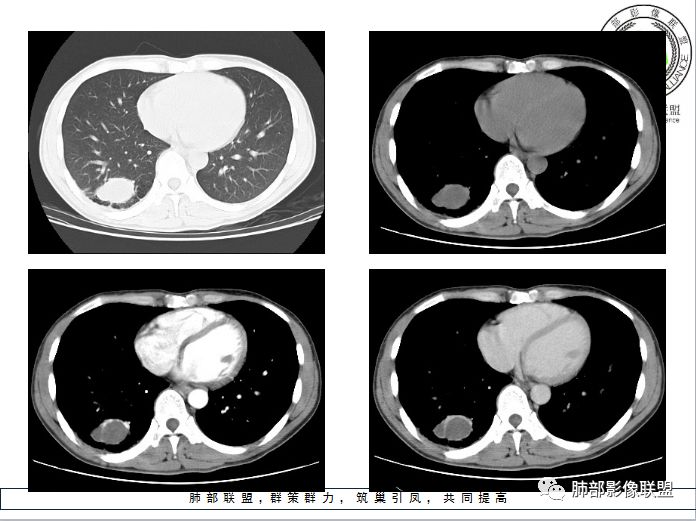

右肺下叶囊性病变,边缘光滑,薄环状强化,内壁较光滑

血管贴边

周围多发长索条

远端有斑片状条带状高密度影,周围肺气肿

附近胸膜增厚,内有血管影

南大病变影像分析:

这个病变和大家所想有些差异,这个图像还是不够薄,但是

第一,看支气管,有一条支气管从病变边缘走过,有一条支气管在病灶近端堵塞;说明病变和支气管有关系,一般情况下支气管堵塞应该考虑炎性病变或恶性肿瘤才可以符合,不符合良性肿瘤,当然肺囊肿也可以,因为它是先天发育变异的。

第二,看强化幅度,内无强化,但是我担心图像并不够薄,目测观察有所偏差,但是现可见薄壁样强化;从这个角度考虑,良性肿瘤就不符合了,如PSP就不太支持了,这个病变远端有分叶、有小尾巴,周围有索条状影,除非PSP合并感染,二元论,否则单纯PSP周围不会有这种表现。

第三,病变旁边胸膜区域有增厚,似乎有些血管增粗,虽然这不是隔离征好发区域;它应该偏内侧一点,但是我们应该最好有重建血管先排除隔离征;从所给图片看,病灶具体走形外面没有看见血管进入,因为是囊性病变嘛。